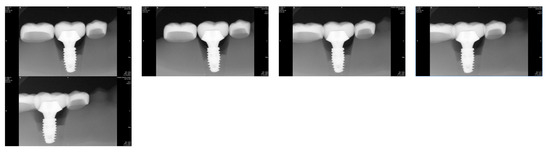

Horizontal distal angulation of the tube head resulted in incremental overlap between the implant restoration and adjacent teeth (Figure 5). At 15°, approximately 5% overlap with the second premolar was observed in all groups, increasing to >10% at 20°. Overlap with the second molar consistently exceeded that of the premolar across all angulations (Table 3).

Figure 5.

Periapical radiographic images taken from left to right with distal horizontal rotation of radiation tube at 0°, 5°, 10°, 15°, and 20° in Group B15.